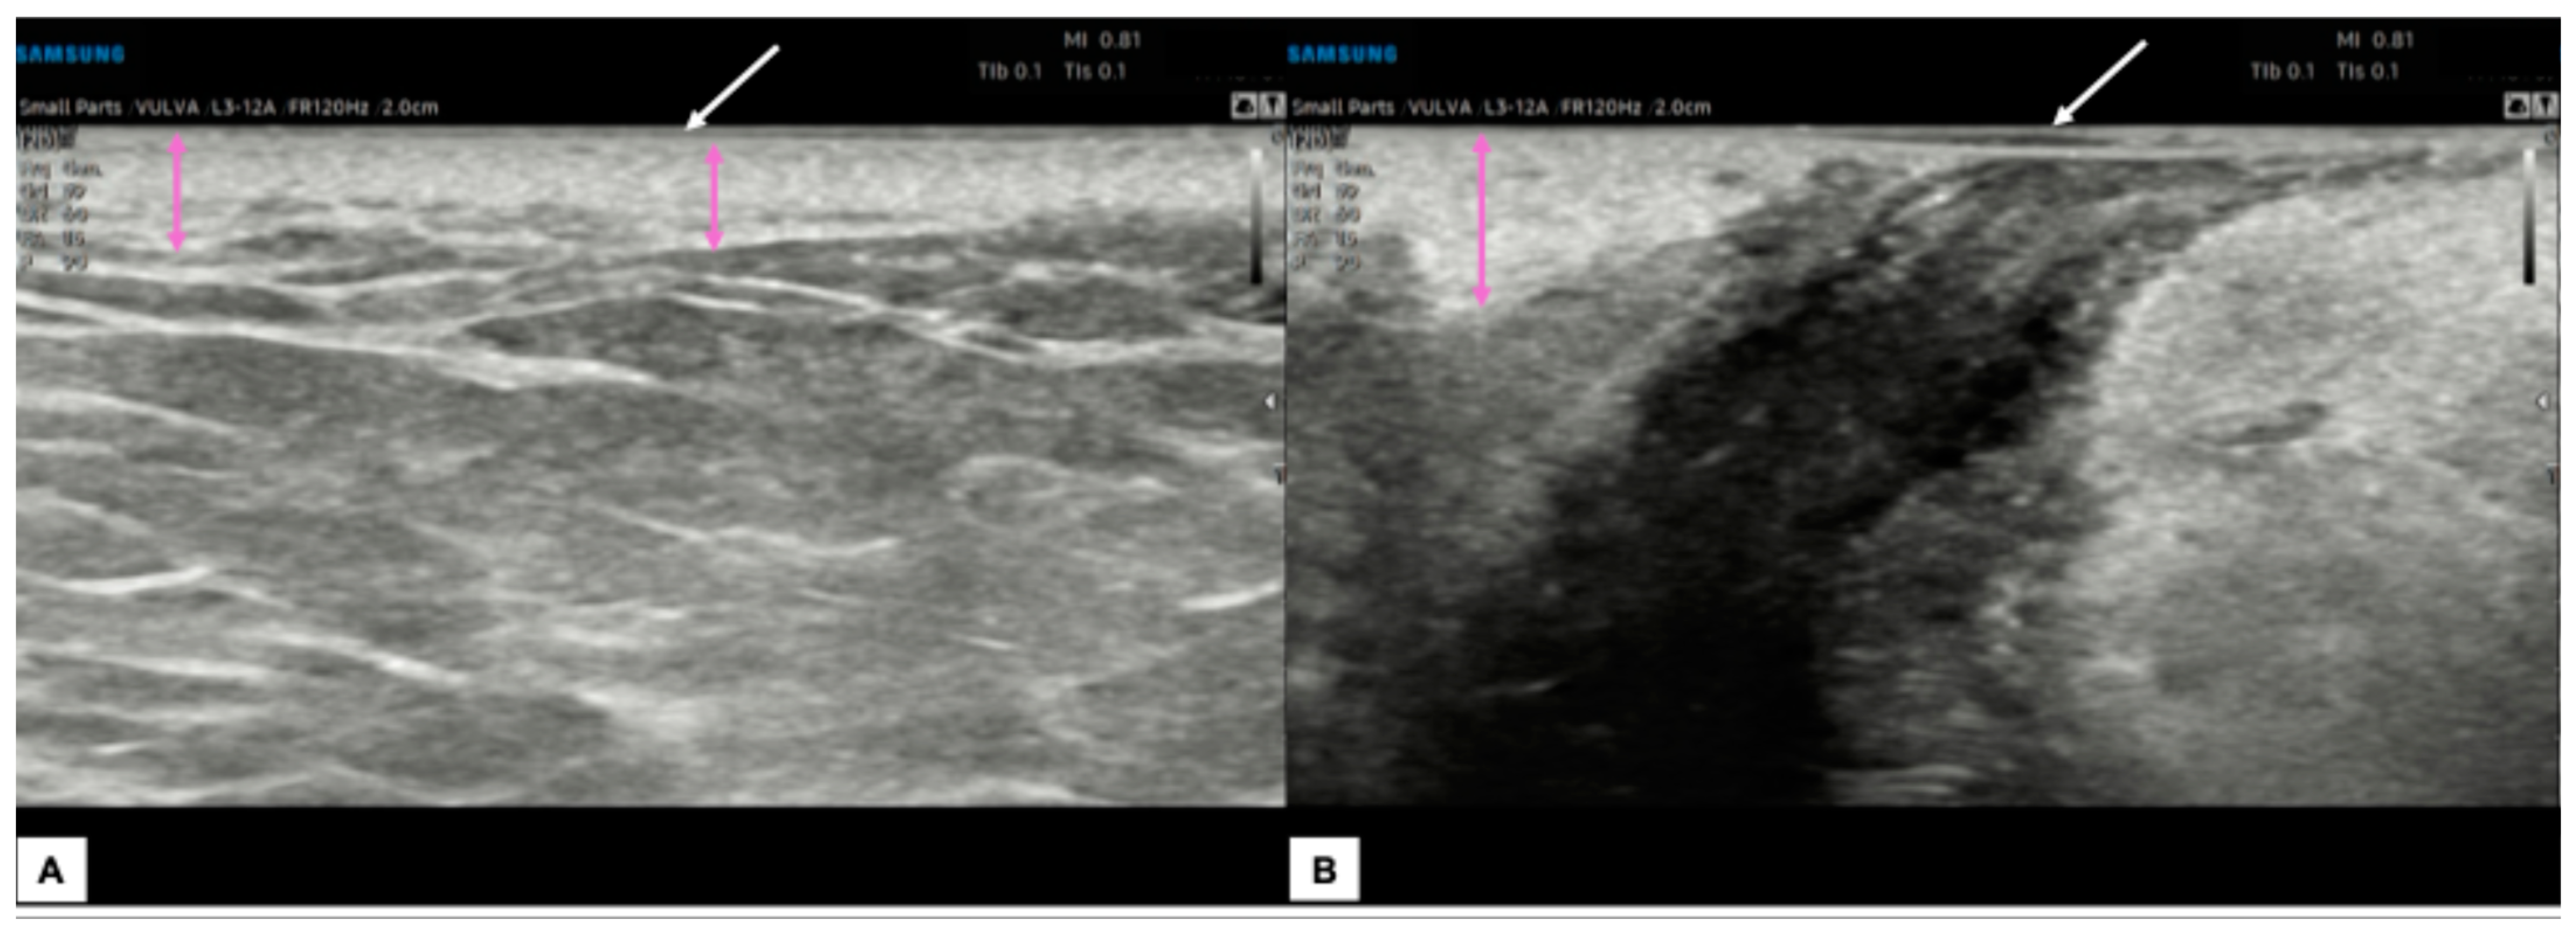

- Measurement from the adjacent most superficial dermal papilla to the deepest point of invasion

- Measurement from the basement membrane of the deepest adjacent dysplastic (tumor-free) rete ridge to the deepest point of invasion, which should be the technique of choice. Because epidermal ridges cannot be distinguished on ultrasonography, our suggestion is to take the lower hyperechogenic line of the epidermal layer as a reference (Figure 10).